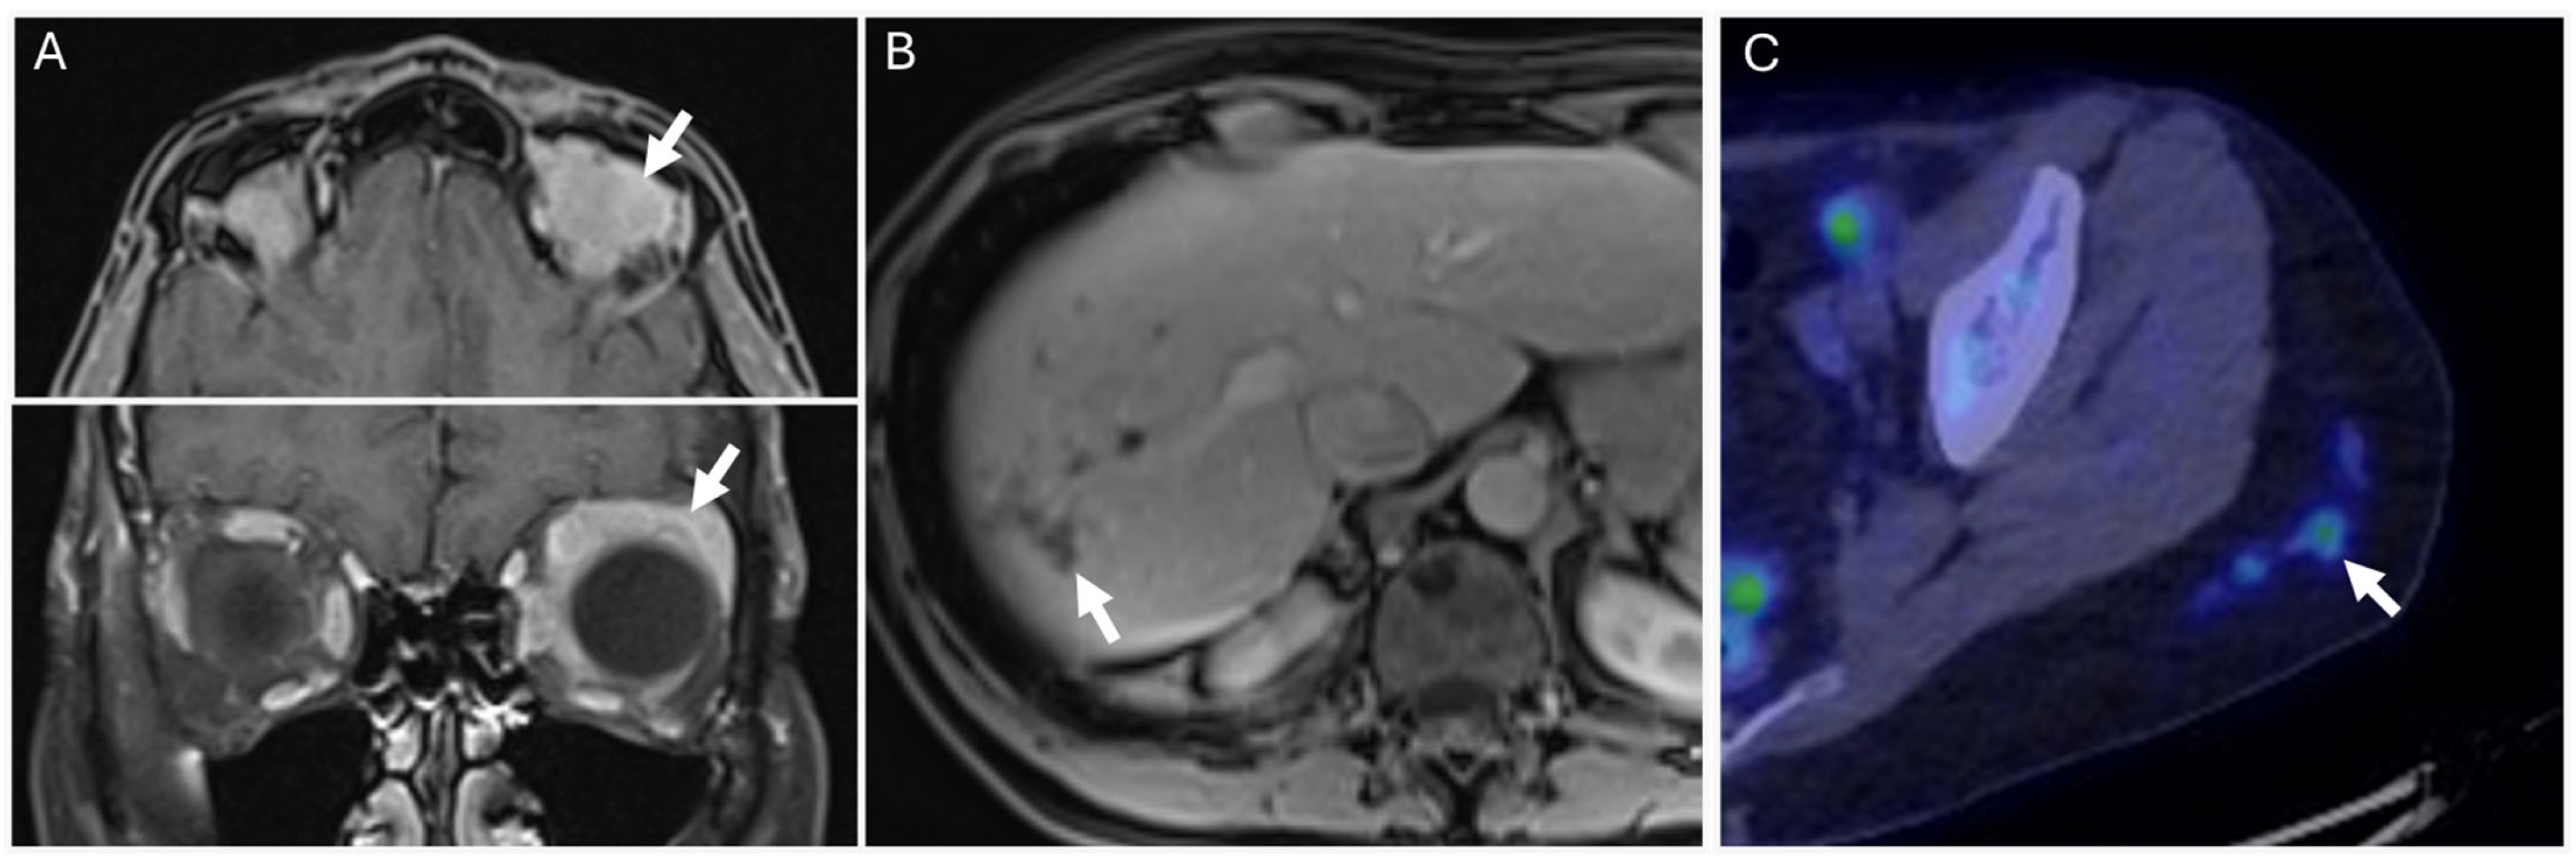

5.2. Necrobiotic Xanthogranuloma (NXG)

5.3. Schnitzler Syndrome

| Monoclonal gammopathy of cutaneous significance |

|